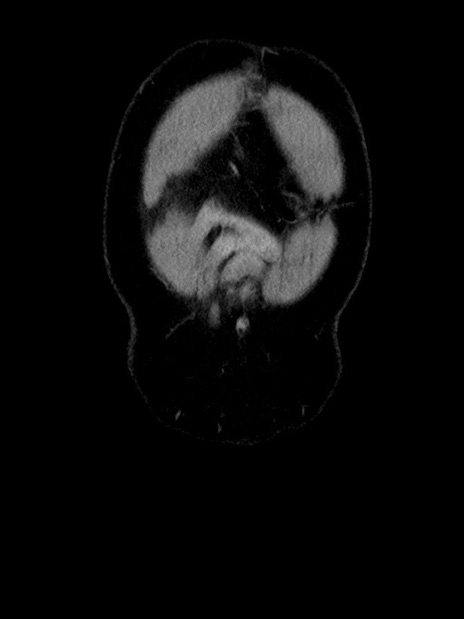

横断像